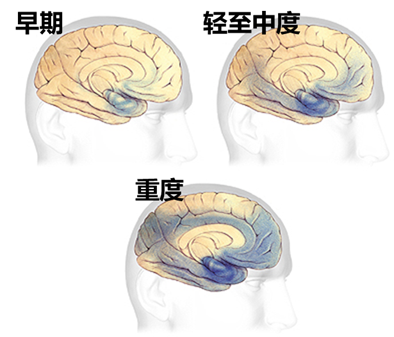

阿兹海默症患者脑部的退变:[3]

早期:脑部退化可能在20年或更早前就开始。最初为影响大脑的学习与记忆、思考与策划区域。

轻至中度:记忆、思考与策划区已形成较多斑块与缠结,导致明显记忆力与思考力退化,并妨碍到日常工作与社交生活。此时,斑块与缠结也会逐渐蔓延到说话与语言理解、自身与周遭对象相关性区域,可能出现性格与行为上的改变。

重度:大部分脑部皮层被严重破坏,患者会失去沟通能力、辨认家人与自我照顾能力等。